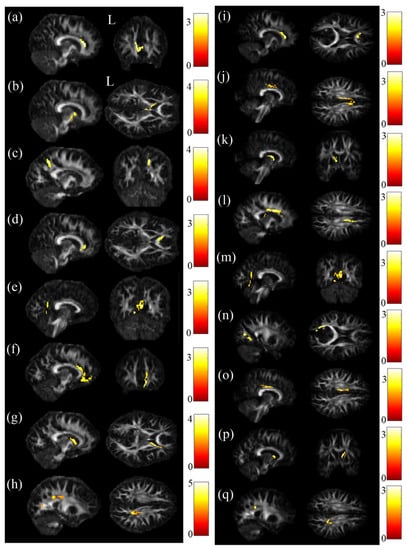

3.2. Voxel-Based Statistical Analysis